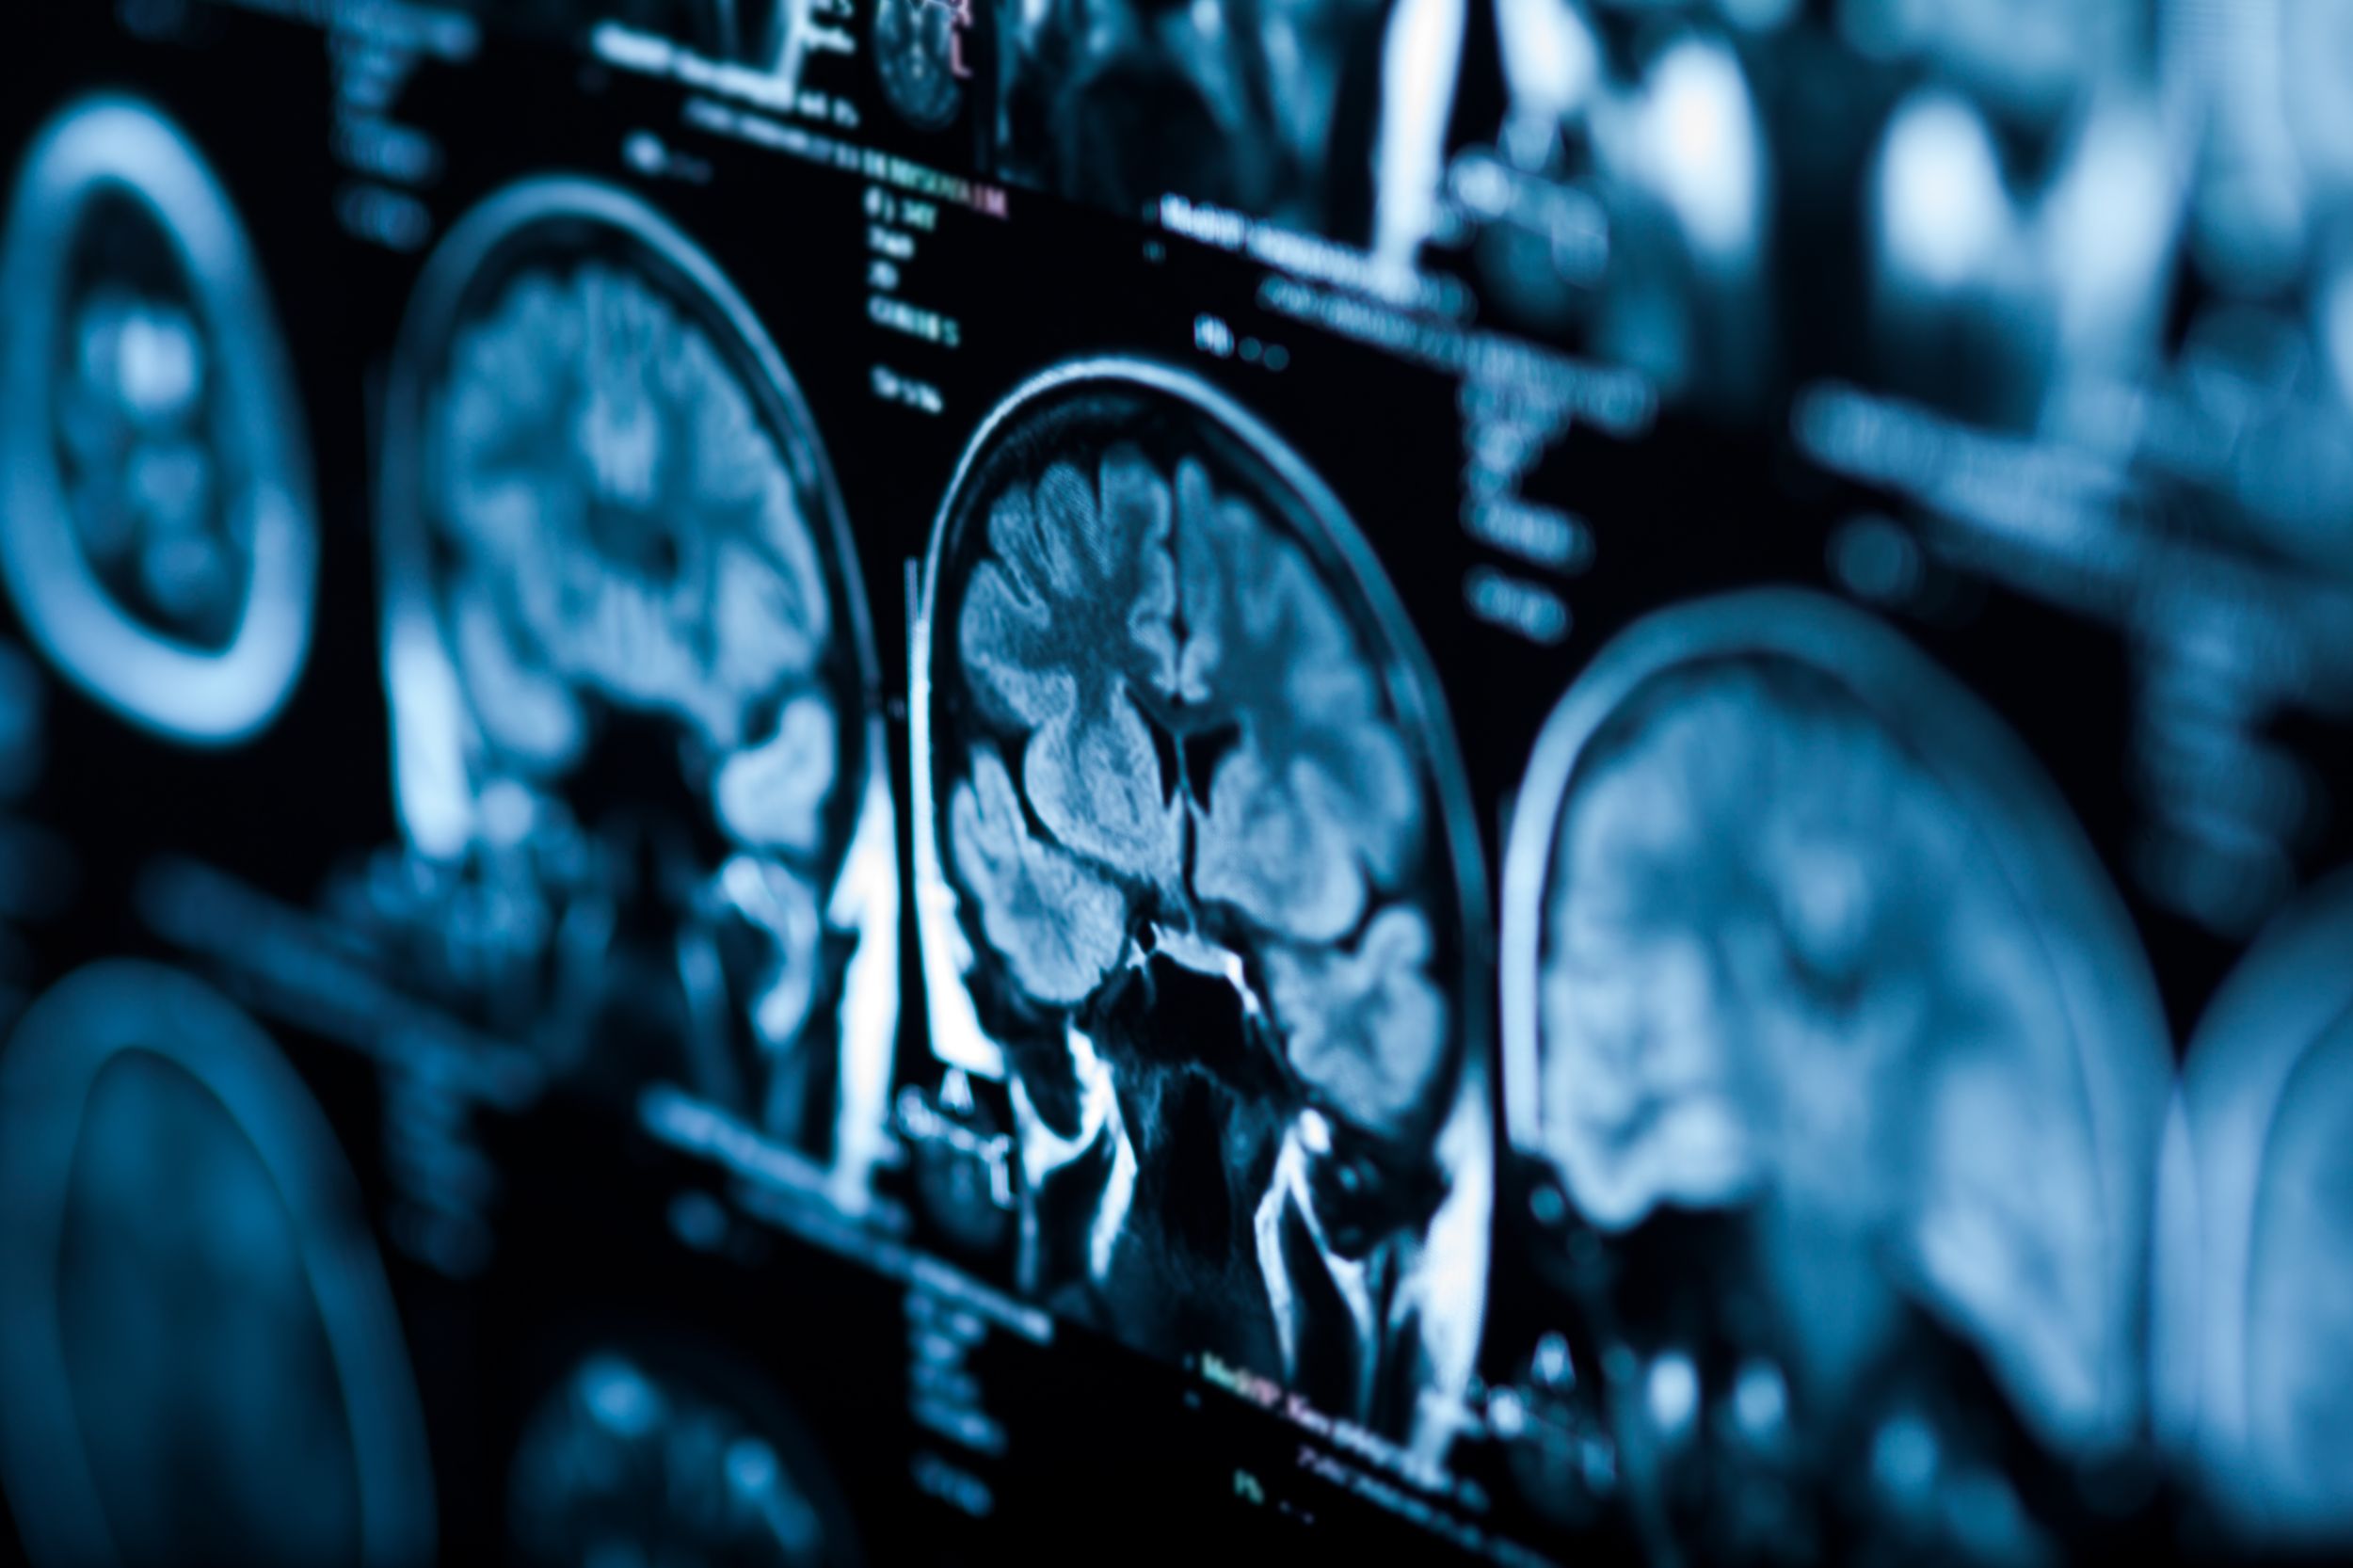

Die wichtigste Untersuchung ist die Magnetresonanztomographie (MRT). Ergänzend können weitere bildgebende Verfahren und Gewebeuntersuchungen (Biopsien) notwendig sein, um die Therapie optimal zu planen.